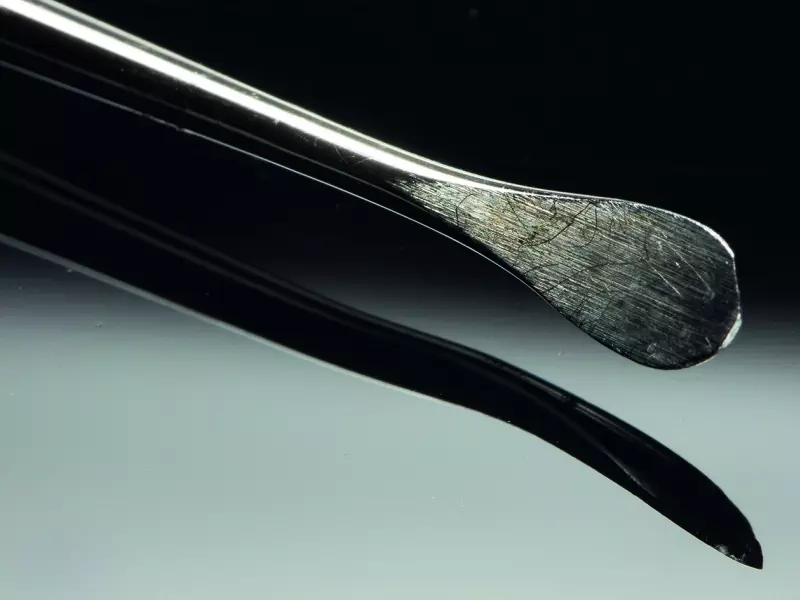

Tkanki miękkie wokół ubytku odpreparowano i utworzono podokostnową kieszeń nad ubytkiem, która była o ok. 2 mm większa niż ubytek. W kieszeni umieszczono kolagenową błonę resorbowalną, odizolowując płat śluzówkowo-okostnowy od światła zębodołu. Zębodół wypełniono substytutem kości i całość pokryto sztywniejszą błoną kolagenową niemającą po założeniu do zębodołu tendencji do zapadania i nierwącą się przy zakładaniu szwów i o stosunkowo długim, bo wynoszącym 6 miesięcy, czasie resorpcji. Całość unieruchomiono przez założenie resorbowalnych szwów.